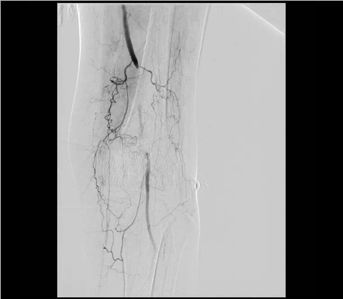

股動脈閉塞